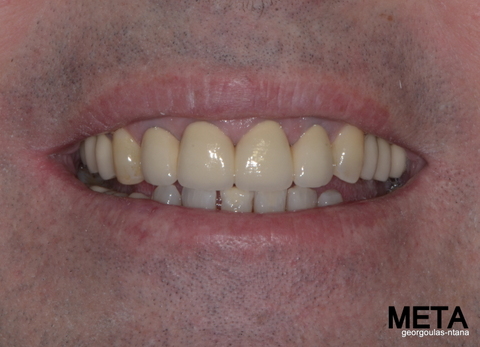

ΟΛΙΚΗ ΑΠΟΚΑΤΑΣΤΑΣΗ ΑΝΩ Κ ΚΑΤΩ ΓΝΑΘΟΥ ΜΕ ΕΜΦΥΤΕΥΜΑΤΑ, ΑΜΕΣΗ ΦΟΡΤΙΣΗ Κ ΑΝΟΙΚΤΗ ΑΝΥΨΩΣΗ ΙΓΜΟΡΕΙΟΥ